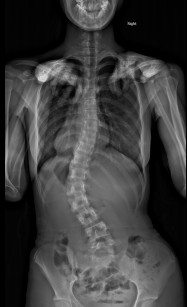

思春期特発性側弯症の全脊椎レントゲンで背骨が大きくSの字に曲がっています。最も曲がっている箇所は80°で、高度側弯に分類されます。後方からの脊柱側弯矯正術で真っ直ぐになっています。

また、側弯の患者さんは一般的にフラットバックと言って背骨の生理的後弯(背中の丸み)が失われています。この症例も胸椎後弯角は5°で典型的なフラットバックを呈しています(正常は20°~30°程度です)。この影響は頸椎の形態にも影響を及ぼし、この症例も頸椎が既に後弯(正常は前弯)しています。(黄色矢印)